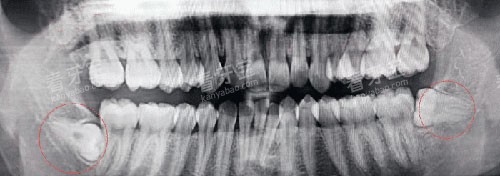

决定价格的头一要素,武断是智齿的难易程度。医生会根据全景X光片,把你的智齿归个类,这直接关联到手术时间和技术复杂度。

这才是大多数人的烦恼来源!阻生智齿就是没能正常萌出,卡在了骨头或牙龈里。它又分好几种:

近中阻生: 智齿向前倾斜,顶住了前面的邻牙,容易导致邻牙蛀牙。

水平阻生: 智齿完全“躺平”长在牙槽骨里,这是拔除难度和创伤都比较大的一种。

完全骨埋伏: 智齿完全藏在牙槽骨里,连头都没露出来,需要切开牙龈、去除部分骨头才能找到它。